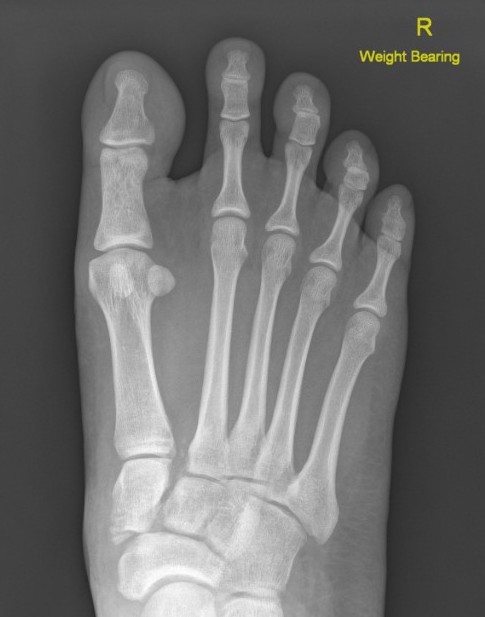

Weight bearing xrays

- weight bearing xrays more sensitive at detecting subtle Lisfranc instability

Increased widening of inter-metatarsal distance on weight bearing views